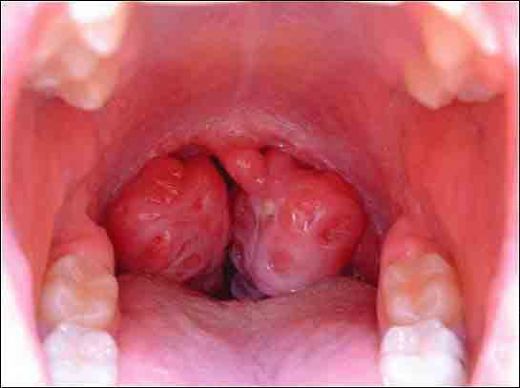

Bademcik ameliyatı, tıpta tonsillektomi olarak bilinen bir prosedürdür. Bu ameliyat, bademciklerin iltihaplanması, enfeksiyon, veya diğer sağlık sorunları nedeniyle gerekli görüldüğünde uygulanır. Ancak, her cerrahi işlemde olduğu gibi, bademcik ameliyatının da belirli riskleri ve sonrası için dikkat edilmesi gereken faktörler bulunmaktadır. Bademcik Ameliyatının Nedenleri Bademcik ameliyatı genellikle aşağıdaki nedenlerden dolayı yapılır:

İyileşme Süreci Bademcik ameliyatından sonraki iyileşme süreci genellikle 1-2 hafta sürer. Bu süre zarfında hastalar, boğazda rahatsızlık, hafif kanama veya enfeksiyon belirtileri yaşayabilir. İyileşme sürecinin sağlıklı bir şekilde geçmesi için:

Sonuç Bademcik ameliyatı, belirli sağlık sorunları için etkili bir tedavi seçeneği sunmaktadır. Ancak, ameliyat öncesi ve sonrası süreçte dikkat edilmesi gereken riskler ve durumlar bulunmaktadır. Hastaların, ameliyat öncesinde doktorlarıyla tüm olası riskler ve beklentiler hakkında açık bir iletişim kurmaları önemlidir. Ameliyat sonrası dönemde ise, doktorun önerilerine uymak ve sağlıklı bir iyileşme süreci geçirmek, başarılı bir sonuç almak açısından kritik öneme sahiptir. |